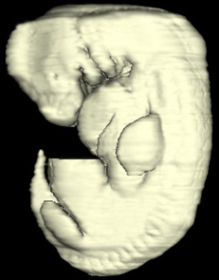

Carnegie Embryo #6502 | Location: 37-01-01

Keywords: L-5 spinal ganglion, T-4 spinal ganglion, abdominal wall, aorta, cephalic edge of metanephric cap, common iliac artery, dermatome, dermatomyotome, dorsal mesentery, gonadal ridge, inferior mesenteric artery, limb mesenchyme, mesonephric duct, myotome, neural canal, neural tube, notochord, peritoneal cavity, postcardinal vein, sclerotome, splanchnic mesenchyme

Source: The Virtual Human Embryo.